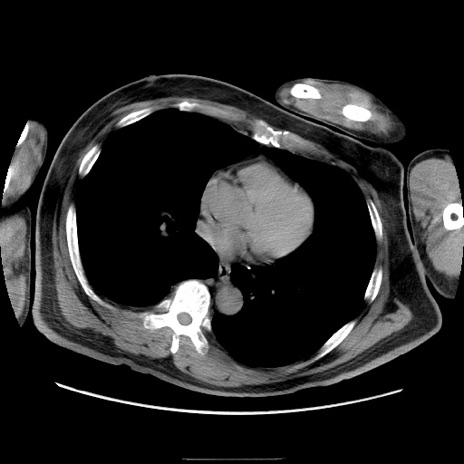

冠状断像

【症例】50歳代男性

【主訴】腹痛

【現病歴】AVMからの被殻出血のため回復期リハ病棟入院中。 本日午後3時頃急に下腹部痛が出現した。

【既往歴】AVM、被殻出血、虫垂炎、高血圧

【身体所見】意識晴明、左半身不全麻痺、会話の理解は良好、36.5°C、腹部:膨隆、全体に板状硬、下腹部正中に圧痛点あり、反跳痛-、筋性防御不明、右下腹部にope scar

【データ】WBC 9400、CRP 0.06